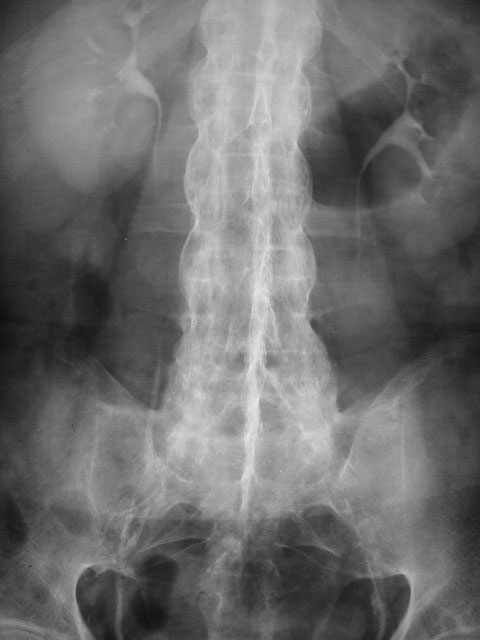

SIGNO DE LA COLUMNA DE BAMBÚ

Signo de espondilitis anquilopoyética en la radiografía de columna. El signo recibe este nombre debido a la morfología de la columna, que recuerda a la caña de bambú. Los cambios que se producen en la columna en la espondilitis son la fusión de los cuerpos vertebrales por sindesmofitos (por calcificación de las fibras externas del anillo fibroso de los discos intervertebrales) y el aspecto cuadrado de los cuerpos vertebrales.